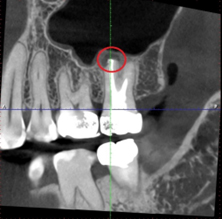

術後經過兩個月的追蹤,從電腦斷層與X光片來看,根尖的發炎反應與治療前相比,黑影有明顯變小許多,患者也表示治療完後牙齦腫脹的感覺有逐漸改善,對於結果非常滿意,也十分感謝黃醫師的幫助與努力。

術前

經前、後X光片對照

可明顯看到黑影變小

術後